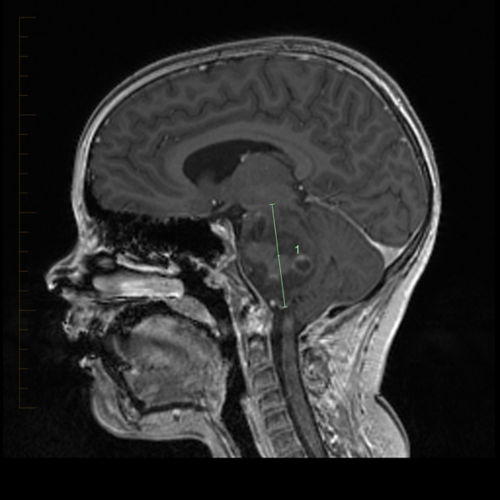

An MRI can be used to diagnose diffuse intrinsic pontine glioma.

• Imaging tests help identify the tumor, see how big the tumor is, and find out what brain areas may be affected. Magnetic resonance imaging (MRI) is the main imaging test used to diagnose DIPG.

Doctors look for key features of the tumor on the MRI to diagnose DIPG:

• The tumor is in the pons.

• It usually involves and expands most of the pons (intrinsic).

• The tumor does not have well-defined borders. It moves into healthy tissue (diffuse).